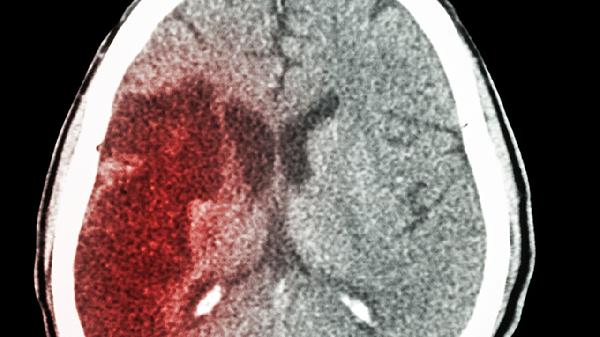

儿童脑出血的常见原因有哪些

儿童脑出血的诱因包括外伤、脑血管异常、血液系统问题、感染以及高血压等。这种疾病常表现出头痛、呕吐、意识不清和抽搐等症状,一旦发现应及时就医,明确原因并进行对症治疗。